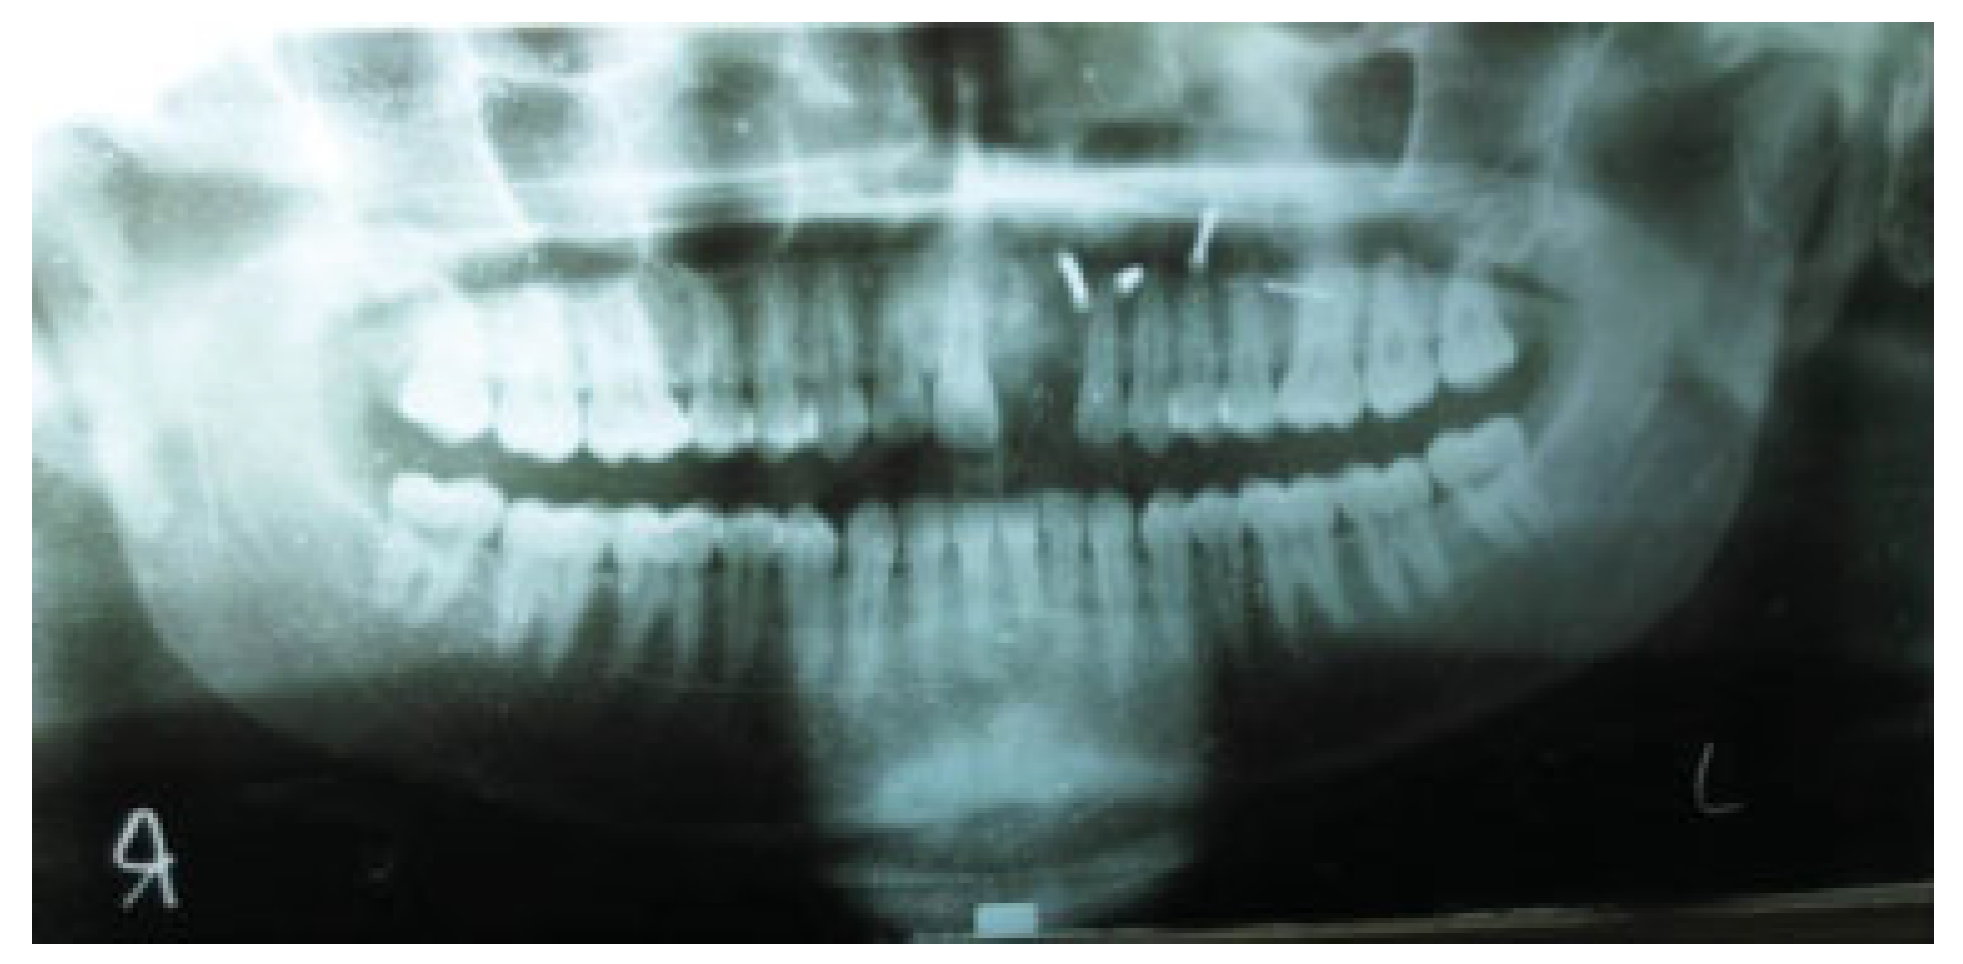

Follow-up of all cases was done for a minimum period of 3 months. Follow-up was done as day −1 (preoperative day), day 1 on operative day, day 10 (10th postoperative day), day 30 (30th postoperative day), and day 90 (90th post-operative day). Orthopantomograms (OPG) were taken on all follow-up visits.

Anatomical reduction was initially assessed by evaluating the functional occlusion in the centric relation of the patient during the postoperative follow-up visits. It was also evaluated by taking pretreatment and postoperative radiographs (OPG) for a period of 3 months on prescribed follow-ups. It was considered positive if overlapping between the fractured fragments was seen in radiographs, and it was considered negative if overlapping was absent.

Bone loss and resorption were assessed by taking a series of radiographs (OPG) for a period of 3 months on prescribed follow-ups. Bone loss was considered positive if bone volume became less on follow-up OPGs and it was considered negative if bone volume remained the same radiographically. Tooth loss was assessed clinically and radiographically on postoperative follow-ups. Tooth loss was considered positive if several teeth in the fractured alveolar process became less, and it was considered negative if the number of teeth remained same.

Preoperatively, all the fractures were unstable, and post lag screw fixation, all alveolar process fracture fragments were stable on all the follow-ups. Fracture stability was seen in all the age groups (Figure 5). All the fracture fragments were found to be anatomically reduced post lag screw fixation on all the follow-up OPGs (Figure 6). There was no marked alveolar bone loss and bone resorption was seen post lag screw fixation on follow-up OPGs (Figure 7; Table 4).

Figure 3. Postoperative orthopantomogram of the patient.